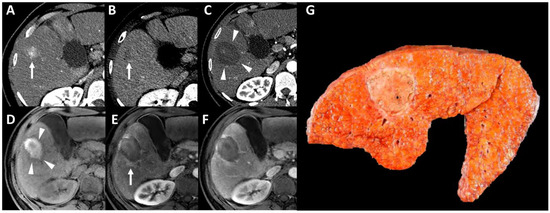

- Mulé, S.; Pregliasco, A.G.; Tenenhaus, A.; Kharrat, R.; Amaddeo, G.; Baranes, L.; Laurent, A.; Regnault, H.; Sommacale, D.; Djabbari, M.; et al. Multiphase Liver MRI for Identifying the Macrotrabecular-Massive Subtype of Hepatocellular Carcinoma. Radiology 2020, 295, 562–571. [Google Scholar] [CrossRef] [PubMed]

- Cannella, R.; Burgio, M.D.; Beaufrère, A.; Trapani, L.; Paradis, V.; Hobeika, C.; Cauchy, F.; Bouattour, M.; Vilgrain, V.; Sartoris, R.; et al. Imaging features of histological subtypes of hepatocellular carcinoma: Implication for LI-RADS. JHEP Rep. Innov. Hepatol. 2021, 3, 100380. [Google Scholar] [CrossRef]

- Feng, Z.; Li, H.; Zhao, H.; Jiang, Y.; Liu, Q.; Chen, Q.; Wang, W.; Rong, P. Preoperative CT for Characterization of Aggressive Macrotrabecular-Massive Subtype and Vessels That Encapsulate Tumor Clusters Pattern in Hepatocellular Carcinoma. Radiology 2021, 300, 219–229. [Google Scholar] [CrossRef] [PubMed]